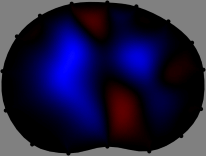

Figs. 3 and 4 compare the performance of the proposed FER method in (20) with the standard regularized least-squares method ((19) when is the identity matrix). The regularization parameter of the standard method was heuristically chosen for its best performance, and the parameter of the FER method was set to be one of three different values . The injection current was 1 mA at 100 kHz, and the frame rate was 9 frames per second. The reference frame at was obtained from the maximum expiration state. The measured data, , represent the voltage differences between each time and . The blue regions, which denote where conductivity decreased by inhaled air, increased during inspiration and decreased during expiration. The FER method with was clearly more robust than the standard method that produced more artifacts originated from the inversion process.

| Standard | |

||||||||||

| FER () | |

| FER () | |||||||||||